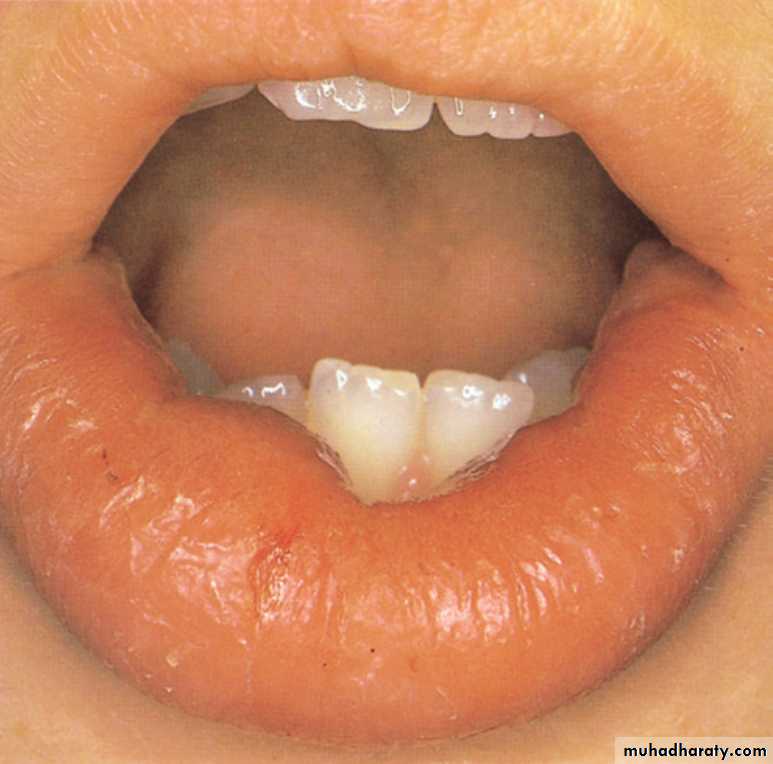

•Gross labial swelling and intraoral mucosal edema with typical histological changes led to the finding of extensive intestinal involvement.

Crohn’s disease

Soft nodular thickening of the oral mucosa is a typical feature and, in this case, was associated with facial swelling and intermittent diarrhea.Crohn’s disease